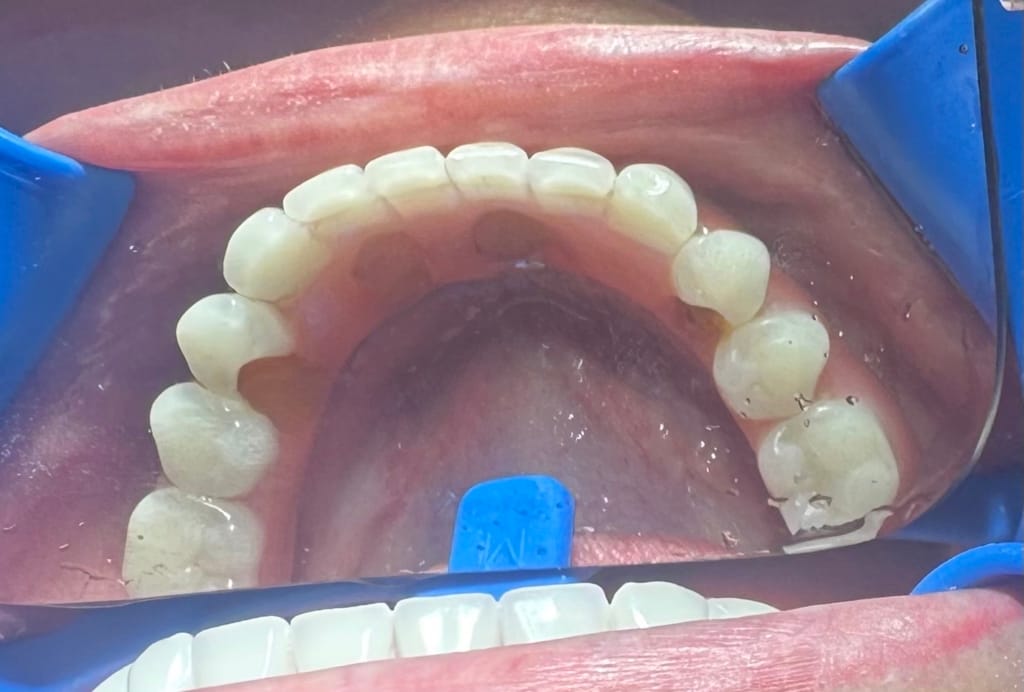

Kaptam néhány fotót, köztük egyet a legutóbbi sérülésről és egy panoráma felvételt.

1. pontosabb mérést kell végezni a fopótlás rágófelszínén…de biztos, hogy túldimenzionálták hátrafelé a rágófelszínt. A túlzott hátsó túlnyúlás miatt túl nagy húzóerő lép fel az első implantátumokon, mely

2. kitépi a túl rövid és beragasztott ideiglenes(!) titán hüvelyt* a fogpótlásból. Bár fémváz van a műíny alatt, de az implantátumokhoz csavarozott titán hüvelyek nem a fémvázzal egyben vannak kimarva / öntve, hanem – egy jóval olcsóbb megoldásként, a fogpótlás csavarozhatóságát biztosítandó – ideiglenes titán hüvelyeket ragasztottak a fogpótlásba. A túl rövid titán hüvely nem tud elég hosszan rögzülni a fogpótlásban: ez egy ekkora hátsó túlnyúlással nem tud már megbírkózni.

Ami szinte még biztos hiba / probléma (szokott lenni): szinte mindenütt átlagos fogsor alaplemez (rózsaszín műíny) alapanyagot és műfogakat alkalmaznak, melyek szeretnék kitörni. Mert olyan erők ébrednek egy ilyen fogpótlásban, melyeket “elviselnI” nem alkalmasak az átlagos protézis alkotóelemek. Erre gyártanak speciális, sokszorosan erősebb alaplemez alapanyagokat és műfogakat – de ezek sokszorta drágábbak és nehezen beszerezhetők hazánkban.